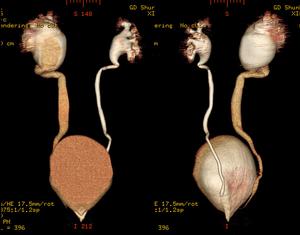

多囊腎 X線表現 |

2、X線檢查:在腹平片中,雙側腎影通常增大,甚至達5倍於正常大小,腎臟長度超過16cm時應疑有此病。在排泄性靜脈造影時行體層攝影有助於確立診斷,體層攝影可顯示透明的多發囊腫。在體層攝影及逆行尿路造影片中,腎臟常增大而腎盞形態則十分怪異(如蜘蛛樣畸形):腎盞增寬、變平、擴大並常彎曲包繞附近周圍的囊腫。這種改變往往在一側腎臟較輕甚至不發生,因而易導致誤診為腫瘤或其他腎疾病。囊腫並發感染時,腎周圍炎可使腎影及至於腰大肌影都模糊不清。血管造影可顯示囊腫周圍彎曲的小血管及囊腫本身所形成的“負”影(無血管分布)。

多囊腎 X線表現